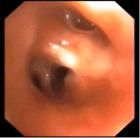

原發性支氣管癌或稱肺癌是最常見的肺部原發性惡性腫瘤。近年來,世界各國肺癌的發病率急劇上升,在工業發達的國家尤為顯著。鱗癌,為最常見類型,約占原發性肺癌40-50%,腫瘤多生長在接近肺門的葉、段支氣管,並有向管腔內生長的傾向,常早期引起支氣管狹窄,導致肺不張,或阻塞性肺炎。鱗癌生長緩慢,轉移晚,手術機會多,但放療和化療治療不如小細胞粉化癌敏感。

鱗癌大多起源於較大的支氣管,常為中央型肺癌。鱗癌的分化程度高低不一,但一般生長較為緩慢。支氣管黏膜上皮細胞長期受紙菸等有害物質的刺激和損傷,首先引致纖毛喪失和基底細胞鱗狀化生。這種癌前期不典型增生病變可持續多年,然後演變成為原位癌,再侵襲支氣管壁其他組織。在此階段雖然痰液中可以查到癌細胞,但尚未呈現臨床症狀。鱗癌的病程較長,較晚發生轉移,且通常首先經淋巴道轉移,到晚期才發生血道轉移。手術切除率較高,對放射及化學療法的敏感度不及未分化癌。

鱗狀上皮細胞癌的形態學特徵是細胞大,呈多邊形,胞漿較多,核染色深。分化程度較高者癌細胞呈復層排列,可見到細胞間橋和角化珠;分化程度中等者細胞大,呈多邊形,但無角化球和細胞間橋;分化程度低者則癌細胞呈小圓形或梭形,排列無層次。